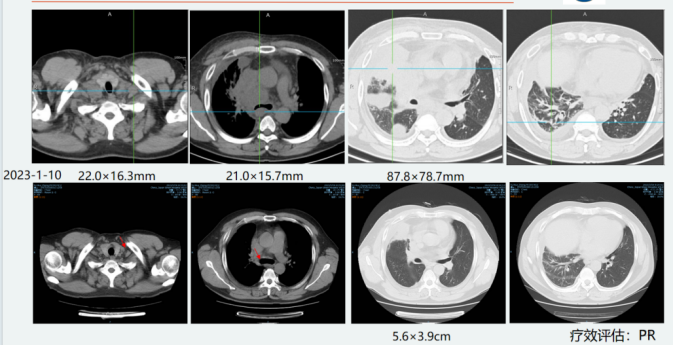

PET-CT(2023-01-10)1. 1. 右肺中叶内侧段伴糖代谢异常增高的团块、结节影,最大 SUV 值为 17.69,最大横截面积约为 87.8×78.7mm,边缘分叶,病变与右侧胸膜分界不清,考虑为周围型肺MT;右侧胸膜受侵;双侧颈内、颈后间隙、锁骨区淋巴结转移最大 SUV 值为 14.35,大小约为22.0×16.3mm;纵隔内、心膈角、膈前、右肺门淋巴结转移,糖代谢较高者最大 SUV 值为 13.88,大小约为 21.0×15.7mm;腰2椎体转移;右肺癌性淋巴管炎可能性大; 2.双侧胸腔积液;心脏增大,请结合临床;心包少量积液。

患者疗效评估-第一次评估-2个疗程后 疗效PR。